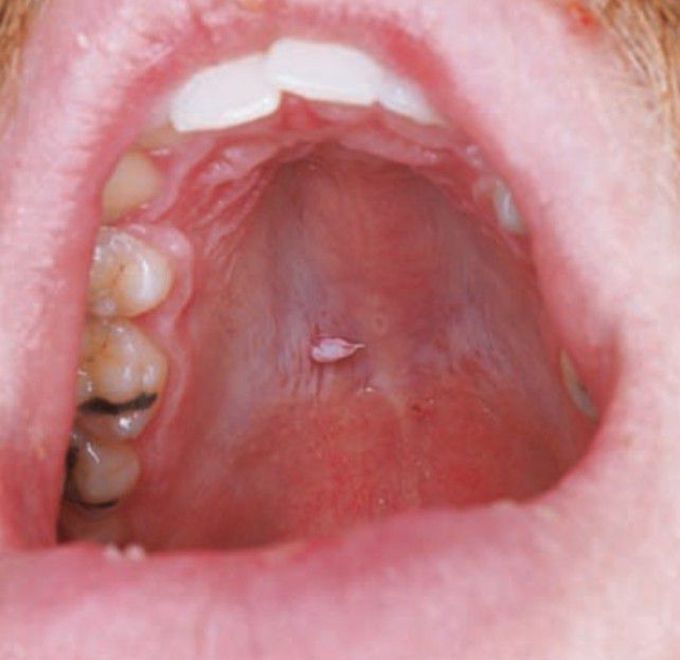

Oral wart

Oral squamous papilloma (including those of the vermilion portion of the lip) is the most common papillary lesion of the oral mucosa and accounts for approximately 2.5% of all oral lesions.